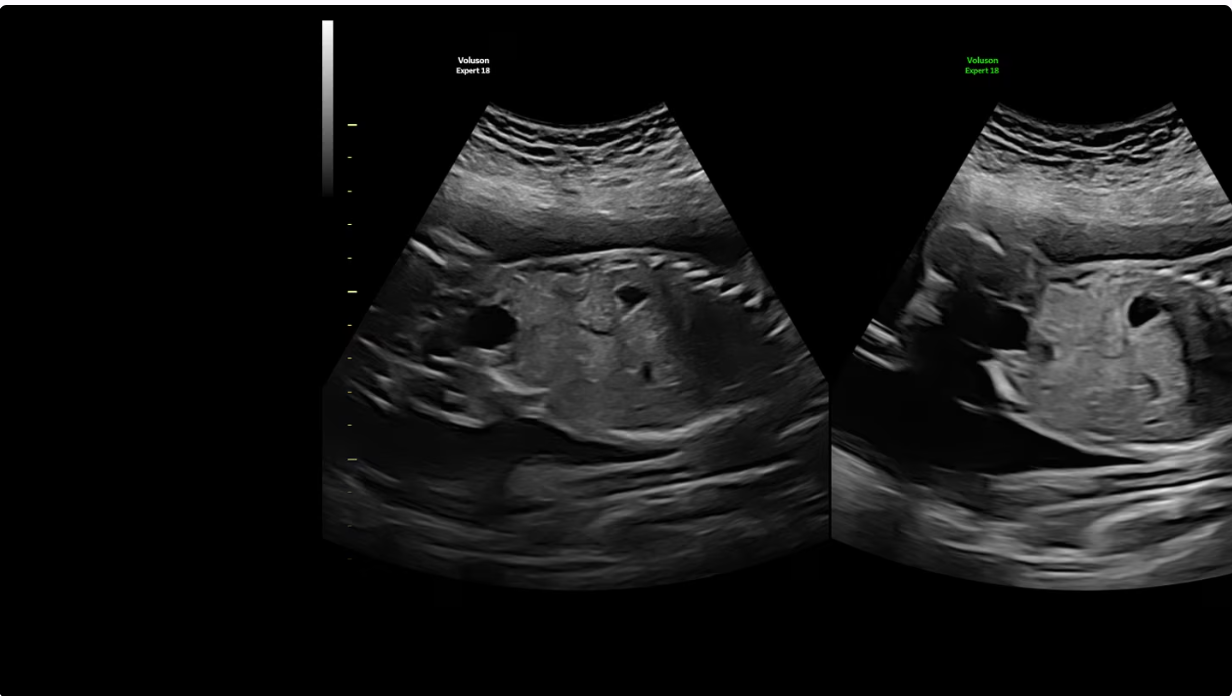

Ультразвуковой аппарат GE Voluson Expert 18 задаёт новый стандарт диагностической визуализации, особенно для сложных акушерских и гинекологических исследований. Созданная на основе усовершенствованной архитектуры Lyric, эта система повышает разрешение и чёткость изображений, обеспечивая превосходные возможности 2D/3D/4D-визуализации для уверенной и точной диагностики. Технология SonoLyst на базе искусственного интеллекта упрощает рутинные исследования, автоматически определяя анатомические особенности плода и оптимизируя измерения, что экономит время и повышает единообразие результатов.

Благодаря таким возможностям, как цветное допплеровское картирование, расширенная объемная визуализация и SonoPelvicFloor, Voluson Expert 18 обеспечивает детальное изображение, имеющее решающее значение для ранней диагностики, вмешательства и клинической уверенности.

С Voluson Expert 18 можно расширить свои возможности и повысить уверенность благодаря превосходному качеству визуализации, основанному на самой передовой архитектуре. Более детальные 2D/3D/4D-изображения и цветное допплеровское картирование для улучшения визуализации в акушерских и гинекологических исследованиях.

- Режимы визуализации: 2D, 3D/4D, цветное допплеровское картирование, энергетическое допплеровское картирование

- Объемная и допплеровская визуализация: улучшает визуализацию сложных анатомических структур, способствуя точной диагностике.

Цветная и допплеровская визцализация